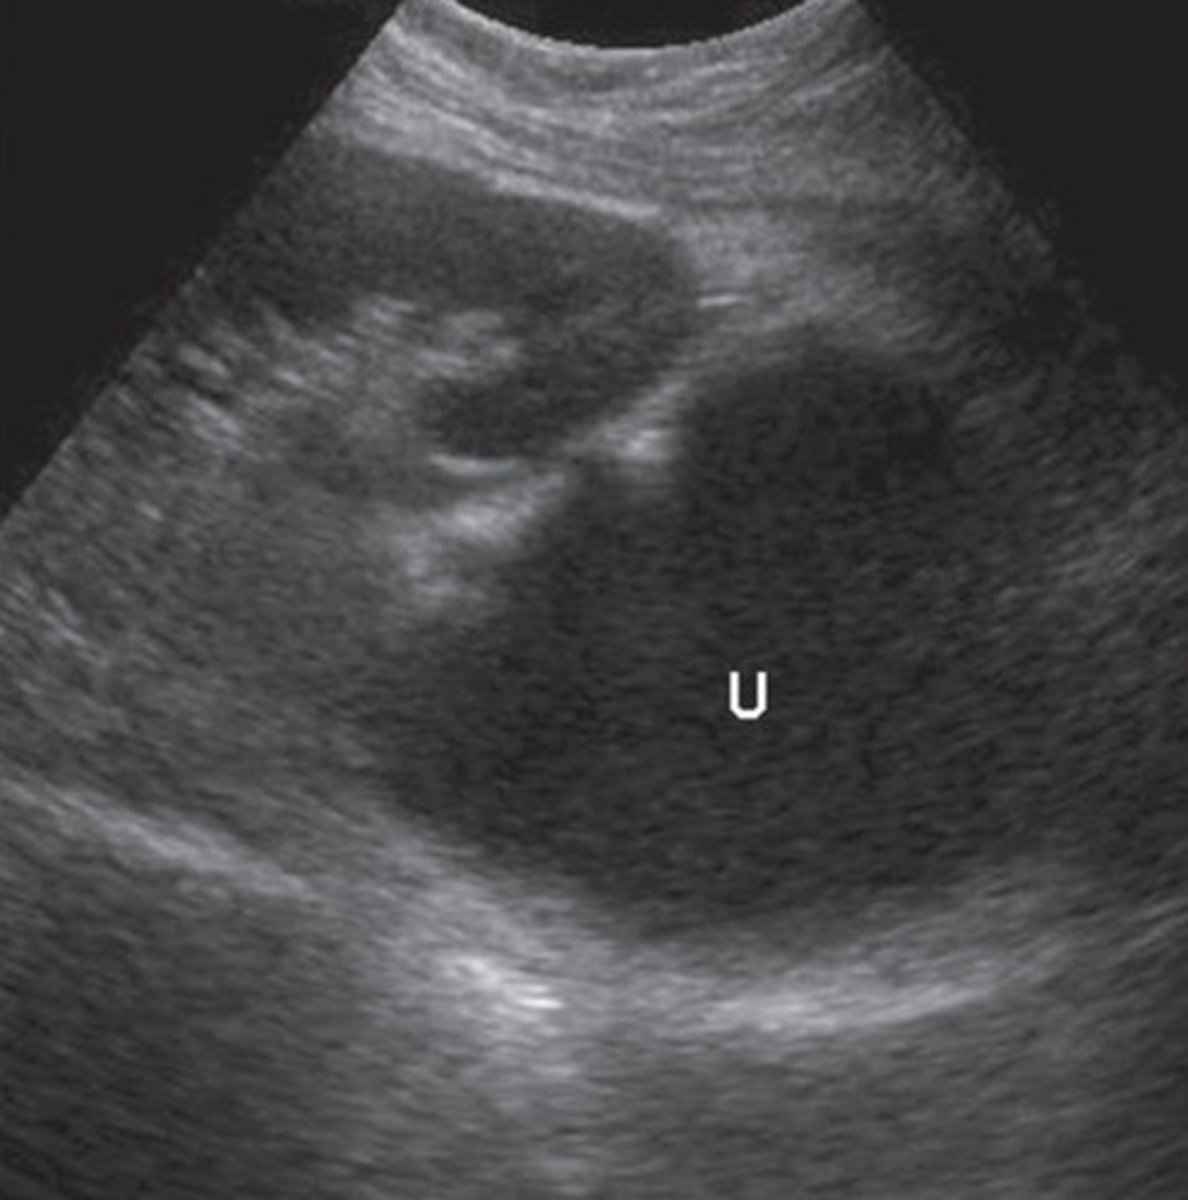

Normal Renal Vein Doppler

Continuous pattern with mild respiratory variations